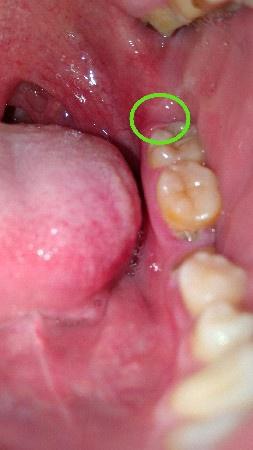

这是智齿冠周炎吗?

最开始左边牙齿最里面的那一颗有些不舒服,而后牙齿周边发疼,现在最里面的肉都非常疼,动嘴就疼。用药酒点了一下,更疼,舌头舔到好像起褶起

用手机开闪光灯拍了一下牙齿。图一图二,这样是智齿冠周炎吗?